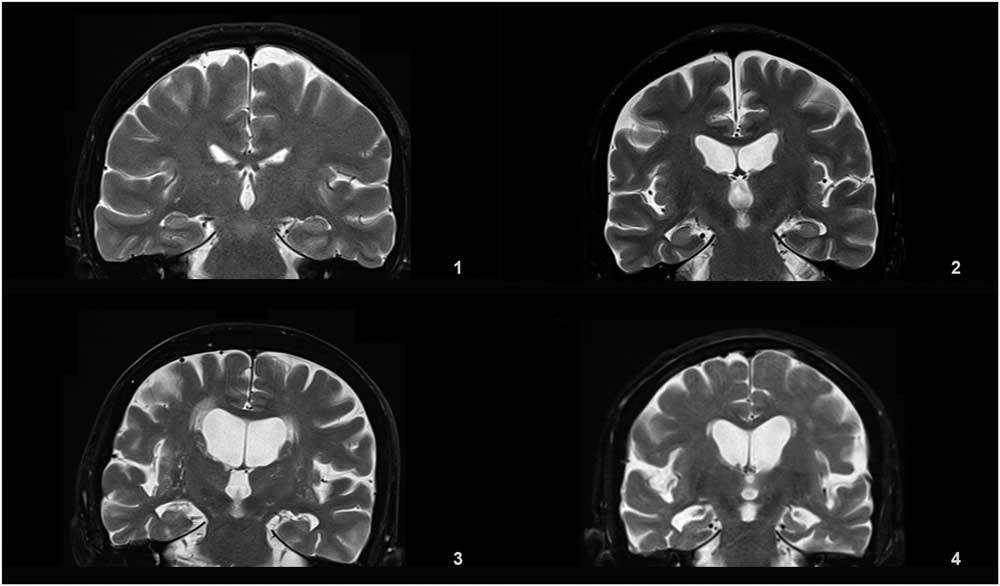

Medial temporal lobe atrophy was graded in a 0-4 range based on the widths of the choroid fissure and temporal horn, and the height of the hippocampal formation on the coronal T2 (TR=6000 ms, TE=90 ms, 3 or 5 mm slice thickness, 0.9 mm gap) slice through the corpus of the hippocampus (at the level of the anterior pons).

Details of the proposed scale are given in Table 1. For grading the SA, VA, and MTA, a reference data set was created from cranial MRIs of 30 subjects who were admitted to the clinic owing to complaints other than forgetfulness, but they were not included in the study (Figures 1–3). An exemplary MRI scan of a patient graded with PWMH=4 and SCWMH=3 can be seen in Figure 4.

Figure 3 Reference MRIs corresponding to medial temporal atrophy grades between 1-4.